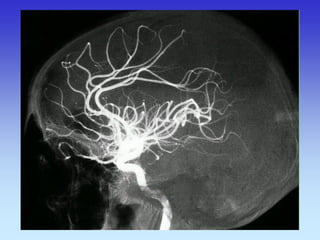

METODE PRIKAZA KRVNIH ŽILA

•UZ-DOPPLER

•DSA

•CTA

•MRA